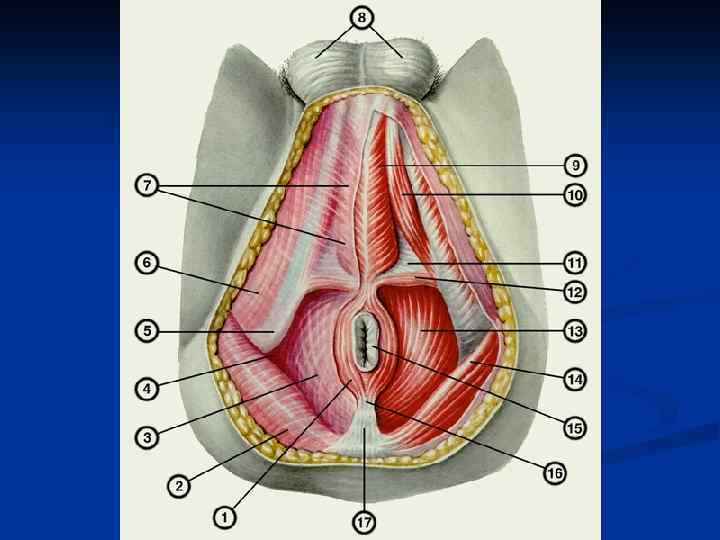

Женские половые органы, organa genitalia feminina

Женские половые органы, organa genitalia feminina